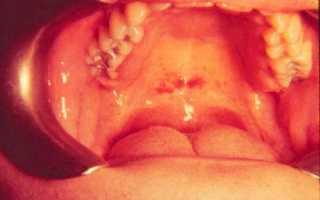

Высокая температура при ангине обусловливает тяжёлое течение общей интоксикации организма. В период разгара лимфаденита у 85-96% больных наблюдаются изменения в глотке, напоминающие или банальный тонзиллит или дифтерийный, или язвенно-пленчатый. В отличие от них моноцитарная ангина начинается с резкого отека слизистой оболочки глотки и элементов лимфаденоидного кольца, что приводит к затруднению носового дыхания, гнусавости, заложенность ушей. В отдельных случаях отек и инфильтрация миндалин достигают значительной степени и вызывают затруднение дыхания.

Сходство симптомов моноцитарной ангины с дифтерийной бывает настолько велико, что более чем в 2/3 случаев ошибочно ставится диагноз дифтерии. При моноцитарной ангине налеты в глотке держатся очень упорно — в течение нескольких недель и даже месяцев. Затруднения при постановке диагноза обычно разрешаются при исследовании крови: лейкоцитоз достигает 10-20х109 /л и выше с преобладанием мононуклеаров (до 60-80%). Заболевание длится 3-4 недели. Сначала регрессирует лихорадка, затем ангина и только после них — лимфаденит. Прогноз благоприятный.